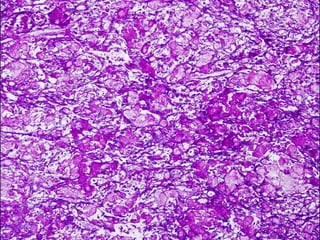

MENINGIOMA ATÍPICO

• Incremento de la actividad mitótica (4 ó más x

10 HPF) o tres o más de los siguientes cuadros

• Incremento de la celularidad

• Células pequeñas con un alto ratio

nucleo:citoplasma

• Nucleolo prominente

• Patrón en mantos

• Necrosis espontanea o geografica

• Se considerara también

atípico a la combinación

de hipercelularidad con

5 o más mitosis x 10

HPF

MENINGIOMA ATÍPICO • Incrementode la actividad mitótica (4 ó más x 10 HPF) o tres o más de los siguientes cuadros • Incremento de la celularidad • Células pequeñas con un alto ratio nucleo:citoplasma • Nucleolo prominente • Patrón en mantos • Necrosis espontanea o geografica

• Se consideraratambién atípico a la combinación de hipercelularidad con 5 o más mitosis x 10 HPF